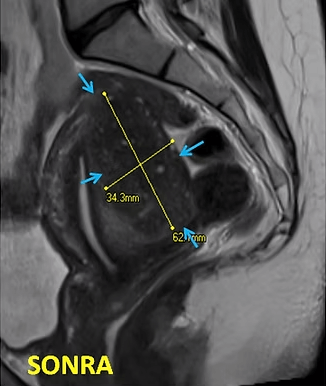

41 yaşında, kabızlık, gaz ve sık idrara çıkma şikayetleri var. Emar’da karını dolduran dev miyom (*) mevcut. Miyomektomi önerilmiş, ancak operasyonda rahimin alınabileceği söylenmiş. Embolizasyondan sonra dev miyomun ve bir başka küçük miyomun öldüğü ve küçüldüğü izleniyor. 7 ay sonra hasta şikayeti kalmamıştır.